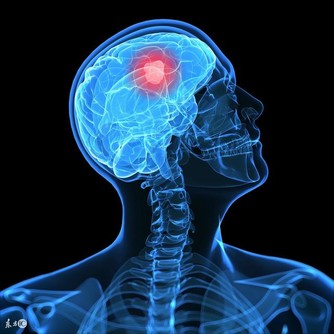

在一年四季之中,氣溫、氣壓、氣流、氣濕等氣象要素最為變化無常的季節是春季。由於氣象要素的多變,在春天常引起許多疾病的複發或增患新病。立春的多發病有肺炎、肝炎、流腦、麻疹、腮腺炎、過敏性哮喘、心肌梗塞、精神病等。因此對於有肝炎、過敏性哮喘、心肌梗塞等患者要特別注意調養預防。